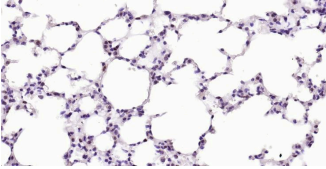

Immunohistochemical analysis of paraffin embedded mouse lung tissue slide using IHC0319M (Mouse PARP Kit).